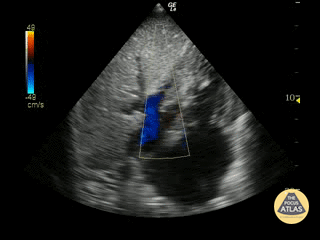

Subcostal View demonstrating mild tricuspid regurgitation Justin Bowra MBBS, FACEM, CCPU Emergency Physician, RNSH et al.